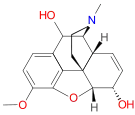

Structures

| Morphides | ||||

|---|---|---|---|---|

Codeine Codeine |

Morphine Morphine |

Oripavine Oripavine |

Pseudomorphine Pseudomorphine |

Thebaine Thebaine |